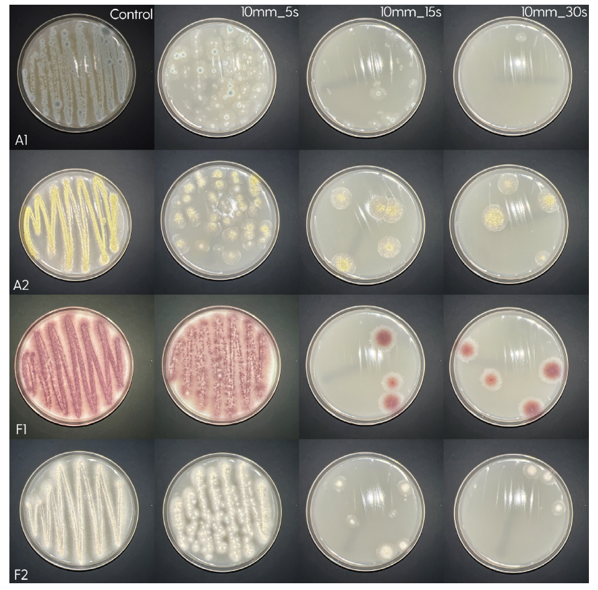

Treatment of the Petri plates inoculated with live bacteria using Ocu-Vet UV-C for 15 seconds at a 10 mm distance.

Photos of the Petri plates, 72 hours after bacterial (Pseudomonas aeruginosa) inoculation.

Image (A) shows positive bacterial growth inhibition (full translucency) at the treatment site after one dose of

UV-C for 15 seconds at 10 mm distance.

Image (B) is the control plate. The blue lines divide the plate into quadrants.

Photos of the Petri plates, 72 hours after bacterial (Streptococcus canis) inoculation.

The image and the inset show complete (positive) bacterial growth inhibition (full translucency)

at the treatment site after one dose of UV-C for 15 seconds at a 10 mm distance.

The blue lines divide the plate into quadrants.

Photo of the Petri plate, 72 hours after bacterial (Moraxella bovis) inoculation. The image shows complete (positive) bacterial growth inhibition (full translucency) at the treatment site after one dose of UV-C for 15 seconds at a 10 mm distance.

The diameter of the area of inhibition, measured with calipers:

– 8 mm (7 mm for Staphylococcus isolates) at 15 seconds.

Microscopic images (4× objective, 5× magnification, Olympus cellSens Standard software) of the central area inoculated with Pseudomonas aeruginosa and treated with UV-C for 15 seconds (A) and the control area (B). A clear demarcation of the treated area can be seen on image (A).

Photos of the Petri plates, 72 hours after bacterial inoculation. Both plates show complete (positive) bacterial growth inhibition (full translucency) at the treatment site after two UV-C doses of 15 seconds at a 15 mm distance. The blue lines divide the plate into quadrants.